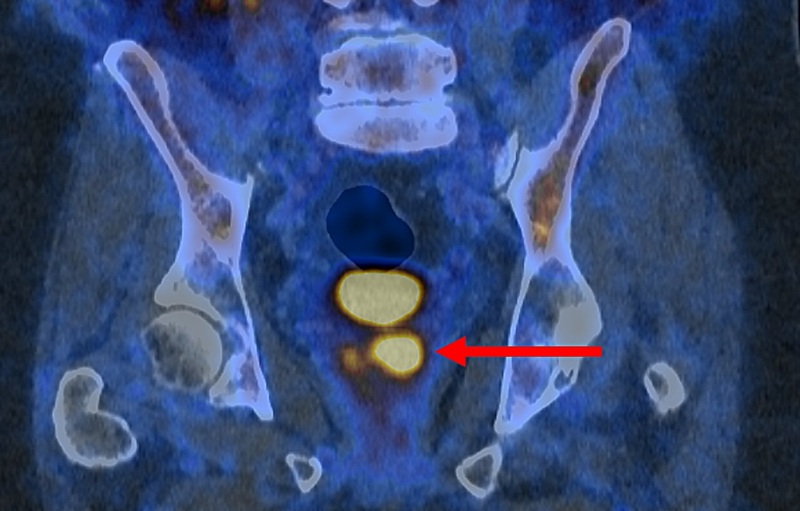

Image: In a new study, MRI elastography demonstrates heterogenous distribution of stiffness in the kidney (Photo courtesy of Anish Kirpalani).

“The MRI allowed us to get a full picture of the kidney, whereas with a biopsy we would only see a tiny piece. We were able to tell that in some parts of the kidney it's very stiff, and in others, it's not stiff at all, which is information we couldn't get from a biopsy,” said lead author radiologist Anish Kirpalani, MD. “Scarring is a big problem for transplant patients, and with MRI we may be able to better guide how kidney transplant patients are treated early on to improve their long-term outcomes.”